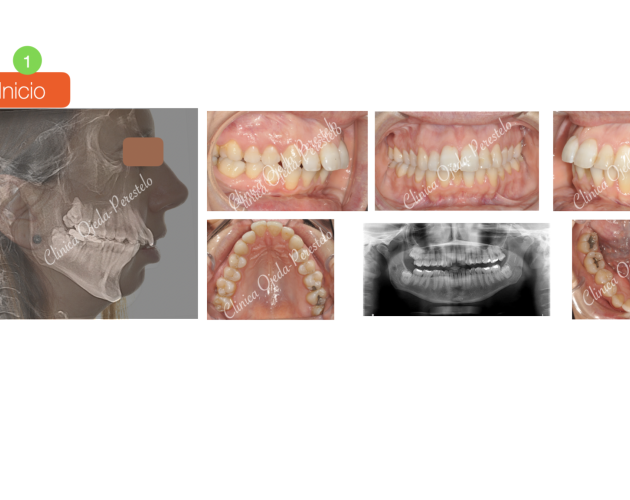

Clase II esquelética con Cirugía de Avance Md Casos de Éxito - Ortodoncia Plástica (Invisalign/Angel) - Adultos

Clase II severa en Mandíbula Hipoplásica Casos de Éxito - Adultos - Cirugía Ortognática

Clase II osea de causa Md con Cara Larga Casos de Éxito - Adultos - Cirugía Ortognática